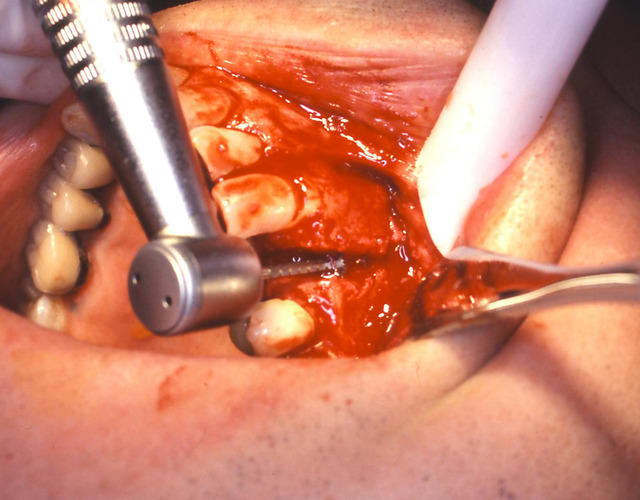

un cas dont j'avais discuté ailleurs avec amibien qui m'avait reproché de ne pas avoir fait la pose en même temps en juin dernier

la pose est de jeudi dernier mon apn est en panne, photo avec le portable, desolé pour le sang mais quand cela saigne il n'y a pas d'échec